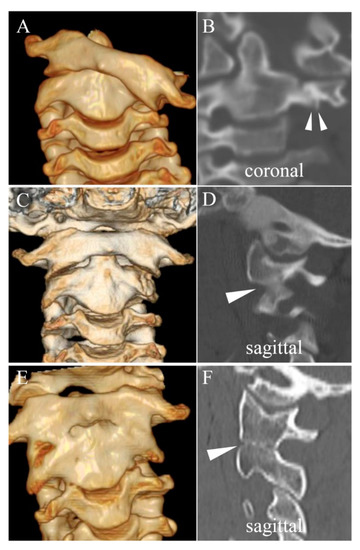

3.3. Direct Osseous Contact of the Facet Joint before and during Halo Fixation

4.1. Spontaneous Osseous Fusion after Halo Traction/Fixation

| SOF | Spontaneous Osseous Fusion of affected vertebrae which is confirmed after remodeling therapy for chronic AARF |

| DOC | Direct Osseous Contact of facet joints which is defined as disappearance of facet joint space between the adjacent vertebrae on sagittal or coronal CT images. |